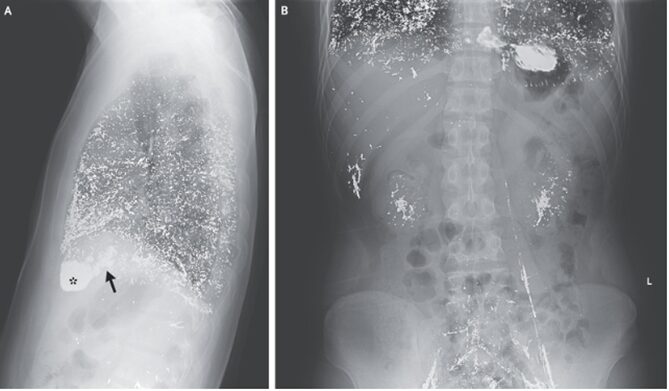

胸部X-p施行され、肺・右心房(矢印)、右心室(*)に透過性の低下した所見を認め総合病院紹介となった。

腹部Xpでは肝臓・腎臓・腸骨静脈および左精巣静脈においても同様の金属密度が示されていた。